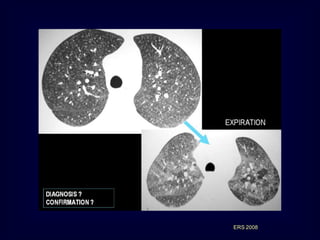

Outpatients with SlowlyProgressive Dyspnea EAA 1. Centilobular nodules • Ill defined (unlike sarcoidosis) 2. Patchy or diffuse GGO 3. Superimposition of (1) and (2) 4. Geographic low density areas on inspiratory HRCT 5. Regional air trapping on expiratory HRCT ERS 2008

• 65.